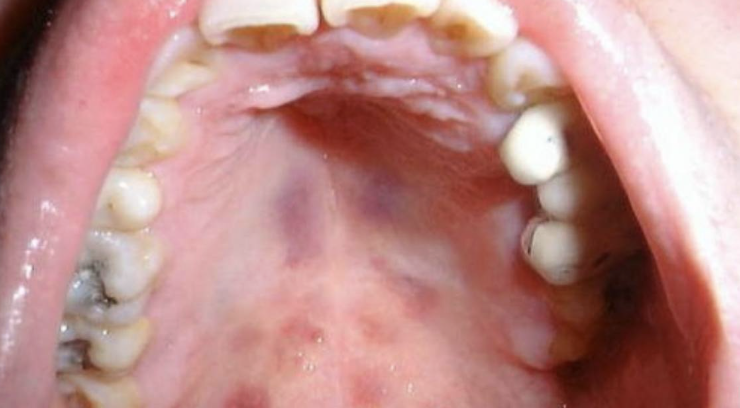

- cánceres, como los linfomas o el sarcoma de Kaposi.